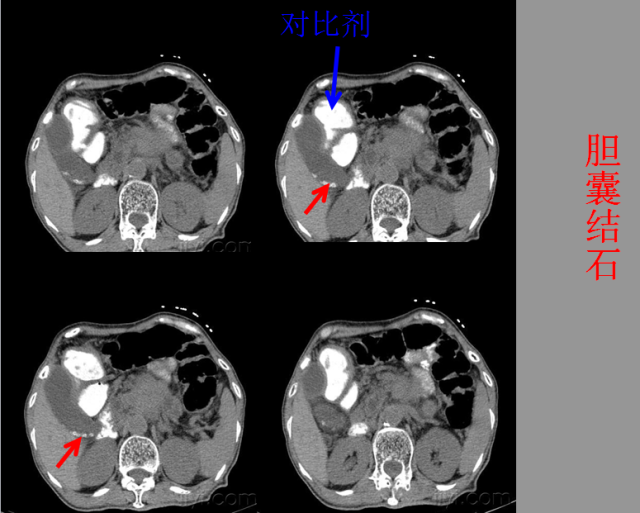

急腹症篇

05